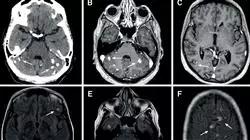

Aunque el diagnóstico neurológico se hace ahora con mayor certeza que en décadas pasadas, sin duda esta precisión ha sido facilitada por el advenimiento de técnicas de investigación diagnóstica cada vez más sofisticadas. Estos avances implican nuevos conocimientos y desarrollos científicos promovidos por la incesante investigación.

Centrado en el contexto real de actuación del médico no especialista y su necesidad diagnóstica y asistencial, en este Curso Universitario en Infecciones del Sistema Nervioso se desarrollarán los conocimientos verdaderamente necesarios en una consulta de primer o segundo nivel, evitando dispersiones en el esfuerzo de aprendizaje.